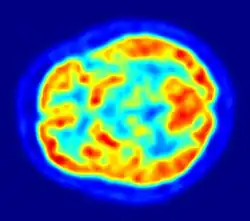

Since one of the focuses of this field is the testing of linguistic and psycholinguistic models, the technology used for experiments is highly relevant to the study of neurolinguistics. Modern brain imaging techniques have contributed greatly to a growing understanding of the anatomical organization of linguistic functions.[2][23] Brain imaging methods used in neurolinguistics may be classified into hemodynamic methods, electrophysiological methods, and methods that stimulate the cortex directly.

Hemodynamic

Hemodynamic techniques take advantage of the fact that when an area of the brain works at a task, blood is sent to supply that area with oxygen (in what is known as the Blood Oxygen Level-Dependent, or BOLD, response).[30] Such techniques include PET and fMRI. These techniques provide high spatial resolution, allowing researchers to pinpoint the location of activity within the brain;[2] temporal resolution (or information about the timing of brain activity), on the other hand, is poor, since the BOLD response happens much more slowly than language processing.[11][31] In addition to demonstrating which parts of the brain may subserve specific language tasks or computations,[20][25] hemodynamic methods have also been used to demonstrate how the structure of the brain's language architecture and the distribution of language-related activation may change over time, as a function of linguistic exposure.[22][28]